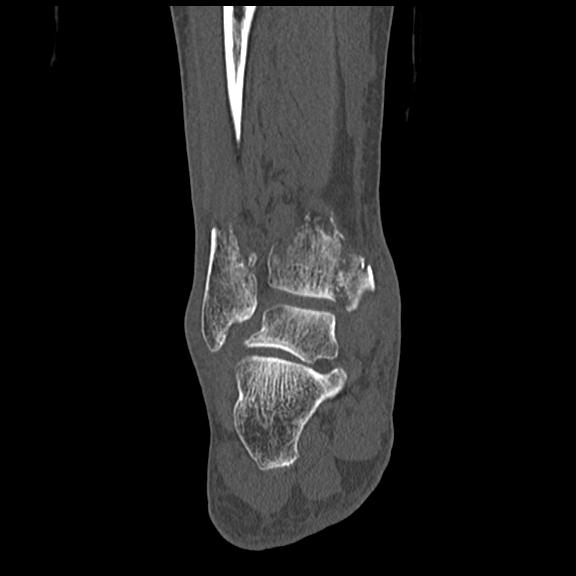

102755 1/4 2R 1/15 2R 右足関節 68歳女性 右三果脱臼骨折